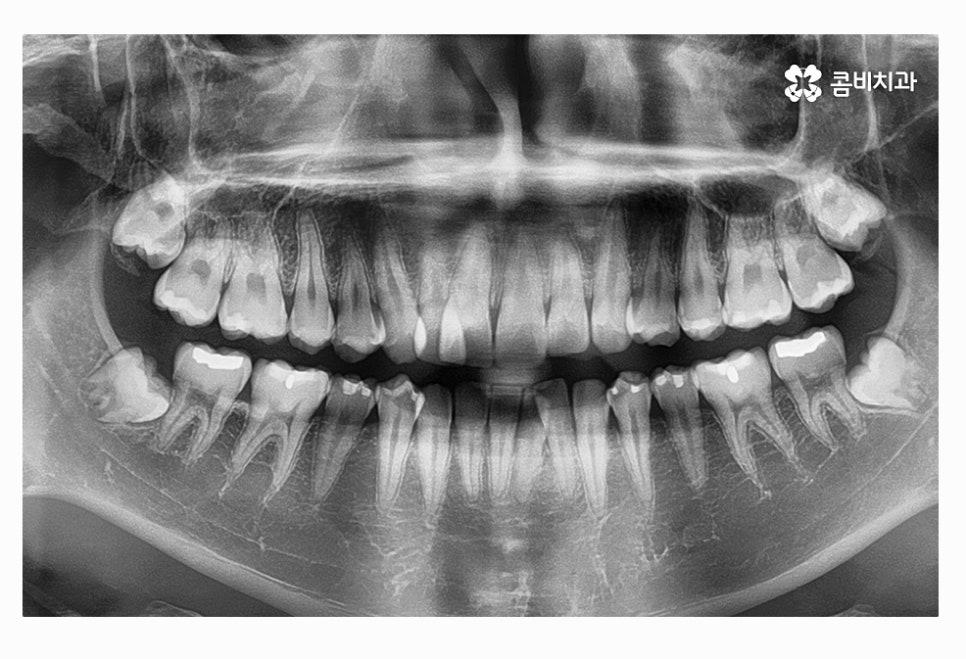

오늘 여러 사례에서 보신 것처럼 사랑니는 다양한 형태로 자라며

꼭 충치가 아니더라도 구강 건강에 악영향을 주는 사례가

많기 때문에 당장 발치를 하는 것을 고민하기보다는

주기적으로 사랑니 상태를 검진하고 스케일링을 통해

청결 관리를 잘하는 것이 큰 문제로 이어지는 일을 막을 수 있어요.

사랑니의 위치와 자라는 방향이 좋지 않은 경우에

평생 건강하게 지켜야 할 어금니의 손상과 수명을

줄어들게 할 수 있기 때문에 발치 시기를 미루지 말고

필요한 경우 의사와 잘 상의하셔야 하며